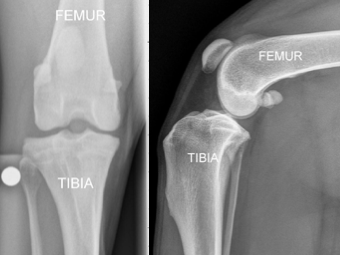

The knee in the dog basically comprises two bones with the femur resting on top of the shin bone (tibia). There is a smaller third bone (fibula), but the fibula is not relevant to this topic.

The radiographs to the right show the front view of a dog knee. The radigoraphs on the right, show a dog’s knee anatomy from the side view. The dog’s femur (thigh bone) is on top of the tibia (shin bone).

The top of the dog’s tibia (referred to as the tibial plateau) is sloped downhill and backwards, typically at about 30 degrees. Because of this 30-degree slope of the proximal tibia, the femur wants to slide off the back of the tibia. These characteristics are shown in the next figure.